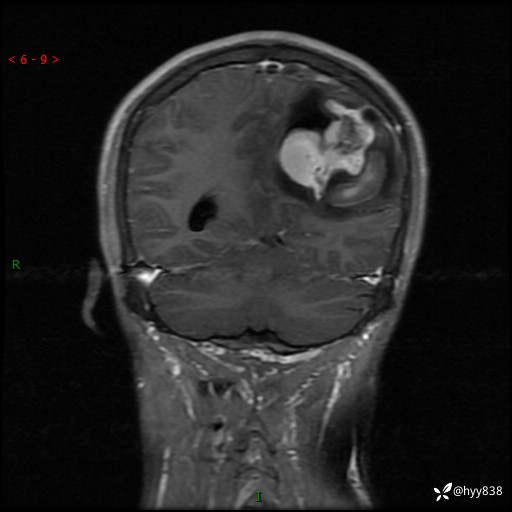

病例年轻小伙,头痛伴呕吐半年,渐进性加重1月。疑难病例,第一次见--结果公布~

性别:男

年龄:21岁

简要病史:头痛伴呕吐半年,渐进性加重1月

颅脑MRI平扫+增强